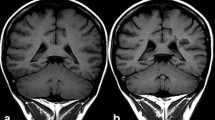

The use of linear extracellular GBCA led to visible changes in SI ratios and measurable Gd depositions in the rat and dog brains [15,16,17,18]. Most depositions were in perivascular foci in the DN and GP [15], with evidence of co-localisation to parenchymal iron [18]. The amount of deposition in rat brains occurred independent of age or sex [17]. Local blood-brain barrier disruptions did not lead to an increase in T1 SI ratios or Gd deposition [19]. Active inflammation showed higher Gd concentration in inflamed areas in mouse brains [20], while the presence of diabetes led to lower brain concentrations [21]. There was a decreased concentration over time in all brain regions, but long-term retention over 1 year occurred preferentially in the rat DN [16]. Despite DN and GP being the brain structures mostly involved by Gd deposition (Figure 1), it should be mentioned that Gd was also suggested to be deposited in other brain areas including pulvinar thalami, pons, frontal lobe cortex and white matter, and cerebellar cortex and white matter, mainly at the level of capillary endothelium and neural interstitium [18, 22, 23]. In addition, increased T1 signal intensity of the anterior pituitary gland, notably not lined by blood–brain barrier, has also been reported after serial exposure to extracellular linear GBCA (Figure 2) [24, 25].

Axial (A, C) and sagittal (B, D) T1-weighted images. Forty-seven-year-old male with multiple sclerosis previously exposed to 14 intra-venous injections of gadodiamide. Globus pallidus and dentate nucleus hyperintensity on unenhanced T1-weighted images due to gadolinium deposition (arrows in A–D). Faint T1 hyperintensity of the pulvinar thalami is also seen (arrowheads in A)

Reproduced from reference 24 under the Creative Commons Attribution 4.0 International License (http://creativecommons.org/licenses/by/4.0/)